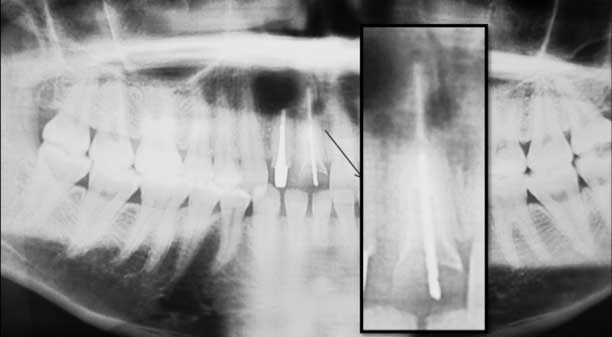

Fig. 2- L’examen radiographique révèle la présence d’une image périapicale radioclaire en regard de la 12 porteuse d’un inlay core et sur laquelle une résection apicale a été effectuée. La 11 présente des parois radiculaires très fines et une petite image périapicale. (Chirurgie endodontique effectuée par Pr Kh AMINE du service de parodontologie du CCTD de Casablanca).

Fig.9- Radiographie rétroalvéolaire de  |

Fig.10 - Le contrôle clinique et radiologique après 6 mois montre une bonne intégration biologique et esthétique de l’implant.